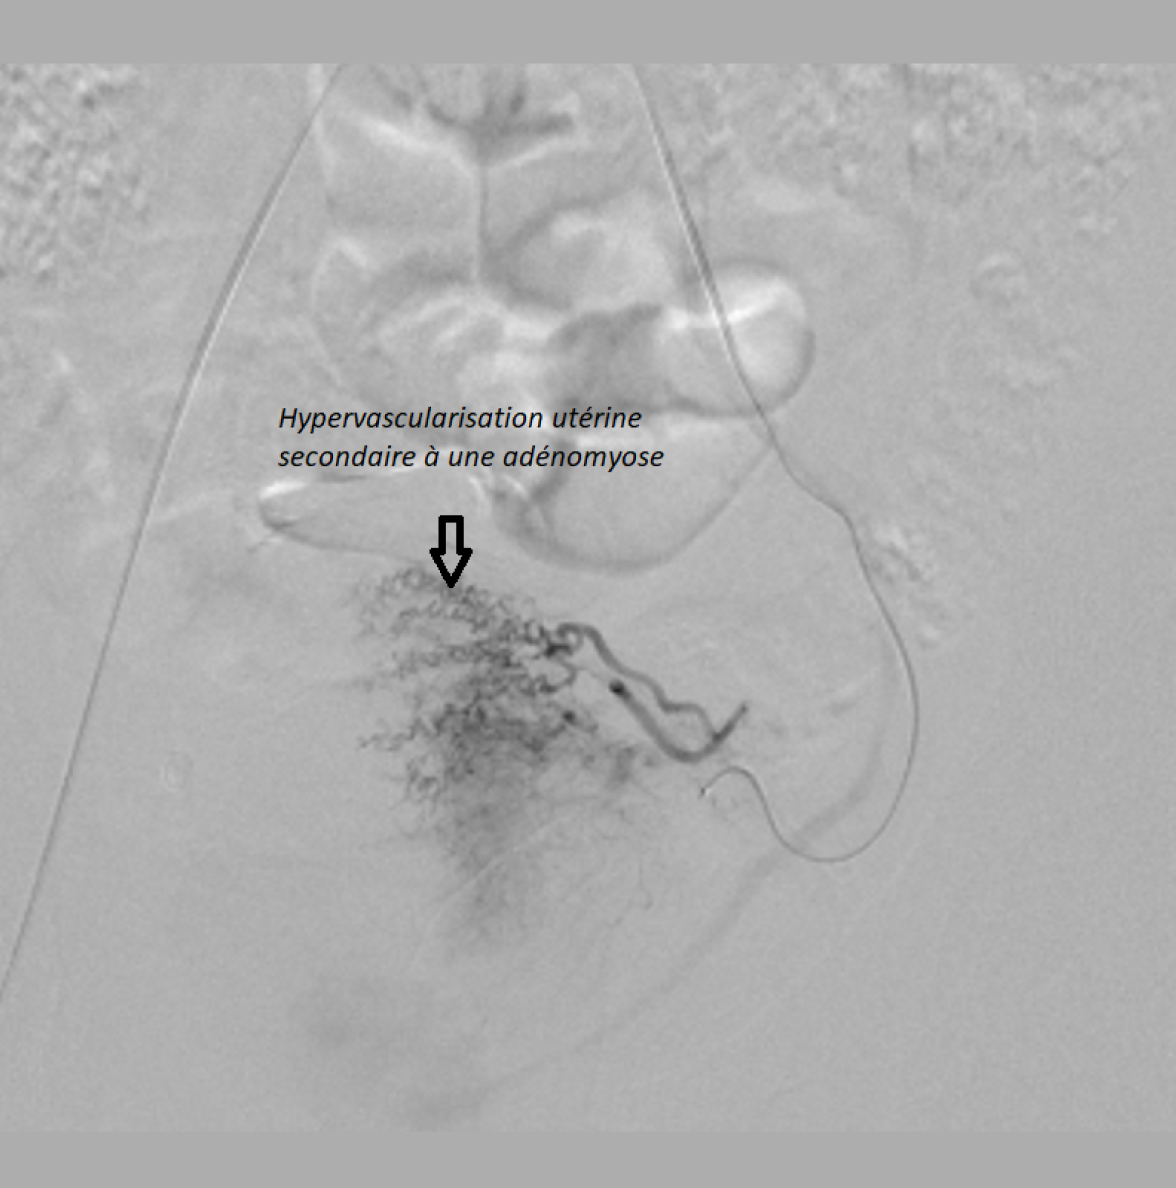

L’embolisation des fibromes utérins et de l’adénomyose est une alternative au traitement chirurgical, réalisée par un radiologue interventionnel. L’objectif est de boucher les artères qui vascularisent l’utérus et ainsi de provoquer l’atrophie des fibromes (une diminution de leur taille) et des lésions d’adénomyose.

• Suite à une anesthésie locale au niveau du point de ponction (poignet ou pli de l’ aine), un cathéter est introduit et l’injection de produit de contraste est pratiquée (ce produit va permettre de suivre la progression de la sonde sous contrôle radiographique).

• L’injection des microbilles destinées à l’occlusion vasculaire est ensuite possible.